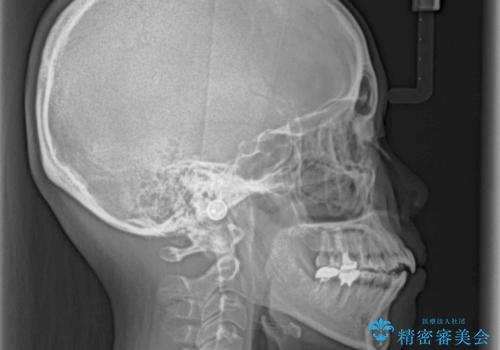

急速拡大装置 狭い骨幅を拡大した上で、顕著なデコボコを改善する抜歯矯正治療

上顎骨よりも下顎骨の幅が広く、更には下顎骨が左側に変位していたため、より良い咬み合わせを達成することを目的として、急速拡大装置を用いて上顎骨を拡大することとしました。